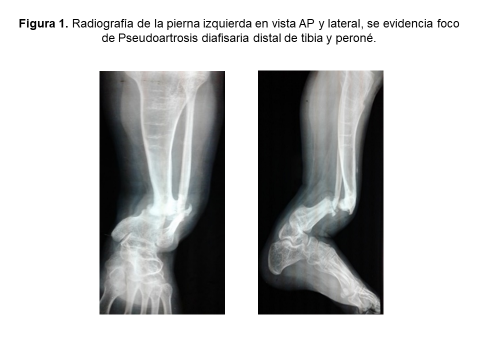

El estudio radiológico inicial evidencia Pseudoartrosis diafisaria distal de tibia y peroné izquierdo (Figura 1), con una longitud de la tibia derecha de 37 cm y una longitud de tibia izquierda de 21cm. Dicha deformidad se presenta desde el nacimiento, por lo que se diagnostica como Displasia Congénita de Tibia y Peroné (Tipo 1, según la Clasificación de EI-Rosasy-Paley-Herzenberg).